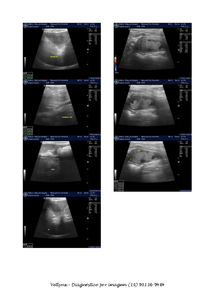

A Manu está com câncer na bexiga. Atualmente o câncer está num tamanho que ocupa quase toda a bexiga. Ela mal dorme pois precisa levantar toda hora para fazer xixi, e quando faz, sai sangue.